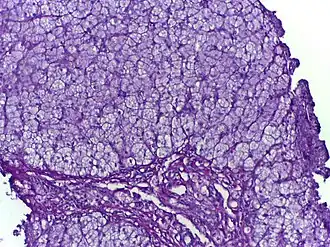

Glycogeenstapelingsziekten (afgekort GSD) of glycogenosen zijn een groep erfelijke aandoeningen van de suikerstofwisseling, waarbij glycogeen niet goed kan worden afgebroken of verwerkt. Elke type heeft een specifiek enzymdefect met daarbij orgaanspecifieke symptomen. Er zijn ten minste twaalf typen glycogeenstapelingsziekten bekend, die door romeinse cijfers van elkaar worden onderscheiden, met uitzondering van type 0: